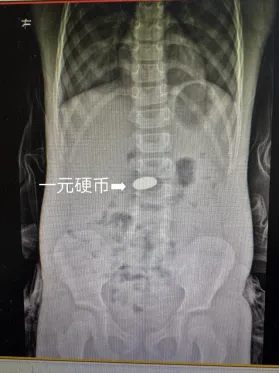

更令人警醒的是一名5岁幼童,因误吞饺子里的硬币被紧急送医。这背后,正是许多家庭“饺子包硬币,寓意好福气”的传统习俗。

“饺中藏币,新年好运”,虽是美好寓意,却隐藏着不容忽视的安全隐患。尤其对于孩子和老人,咀嚼与吞咽能力较弱,一旦不慎吞入硬币,轻则腹痛呕吐,重则堵塞消化道,常需通过内镜甚至手术取出,若已进入肠道则可能需灌肠辅助排出。